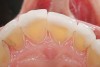

Figure 1   Classic presentation of the bruxism triad. Lateral wear pattern, generalized buccal tooth loss from erosion and abrasion, and history of sleep disruption.

Figure 1